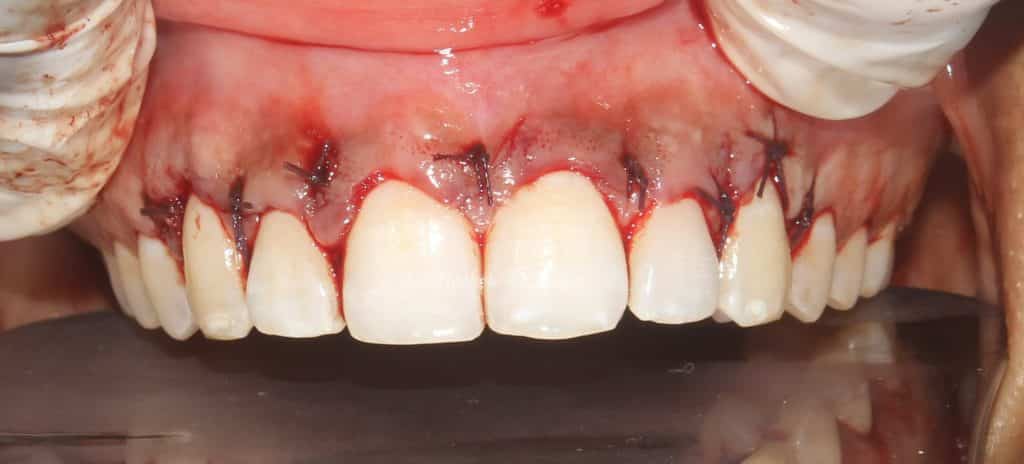

intra oral pic of suturing..